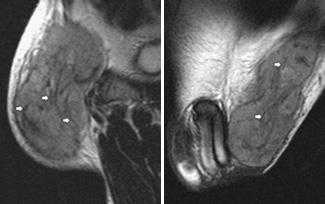

Визуализируются кавернозные тела, окруженные белочной оболочкой (головки стрелок), спонгиозное тело (*) и артерии кавернозных тел (изогнутые стрелки).

Травма полового члена

Определяется нарушение целостности правого кавернозного тела и разрыв окружающий его белочной оболочки (стрелки) с формированием подкожной гематомы –«перелом» пениса.

Болезнь Пейрони

Происходит поражение соединительной ткани с формированием фиброзных локальных утолщений белочной оболочки полового члена и внутрикавернозных перегородок. Синонимы: фиброзный кавернит, пластическая индурация полового члена.

Определяется дорзальная индурация белочной оболочки, значительная дорзальная деформация пениса. Стрелки показывают значительное фокальное утолщение дорзальных отделов белочной оболочки (больших размеров бляшка).

Воспаление спонгиозного тела полового члена (спонгиозит)

Воспалительная инфильтрация вентральных отделов пениса, увеличение в размерах спонгиозного тела.

Опухоли полового члена.

Наиболее часто встречается рак полового члена. Пик частоты встречаемости приходится на 50-70 лет.

В дистальных отделах полового члена определяется гетерогенной структуры опухолевая масса, с инвазией кавернозных тел (черная стрелка). Мелкий метастаз определяется в проксимальном отделе кавернозного тела (маленькая белая стрелка).

Метастатическое поражение полового члена

Этиология- первичные опухоли мочеполового тракта (РПЖ, уротелиального рака).

В анамнезе резекция мочевого пузыря по поводу уротелиального рака 4 года назад. Определяется неоднородной структуры опухоль головки полового члена (метастатическое поражение).

Тромбоз пещеристого тела

Артериальные или венозные причины, ведущие к нарушению кровообращения в кавернозных телах полового члена.

Определяется увеличение в размерах и изменение сигнала от левого кавернозного тела. Кавернозное тело справа без особенностей. Сегментарный тромбоз кавернозного тела.

Фиброзные изменения каверзнозных тел

Происходит формирование фиброзной ткани в каверзнозных телах вследствие длительного нарушения кровоснабжения.

Посттравматические фиброзные изменения, наиболее выраженные в левом пещеристом теле.

Последствия приапизма

Состояние после 2-стороннего шунтирования кавернозных тел по поводу приапизма. Справа удачное шунтирование (нормальные размеры и сигнал от кавернозного тела). Слева шунтирование прошло неудачно, пещеристое тело увеличено в размерах, с признаками ишемии и развивающегося инфаркта.